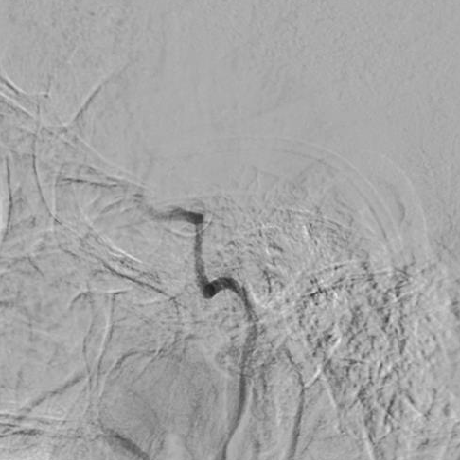

造影可见前交通动脉开放,双侧大脑中动脉显影,左侧颈内动脉末端显影;左侧颈内动脉颈段以远未见显影。

1、造影可见左侧颈总动脉和主动脉弓呈锐角,尝试泥鳅导丝+125cm多功能导管引导8F导引导管超选左侧颈总动脉时,导引导管无法送达,更换6F长鞘超选至左侧颈内动脉颈段,撤出导丝及多功能导管,考虑主动脉弓处张力较大,遂选择具有良好支撑性的React™ 68 远端通路导管替代中间导管。

React™ 68导管内造影见床突段显影浅单,以远未见显影